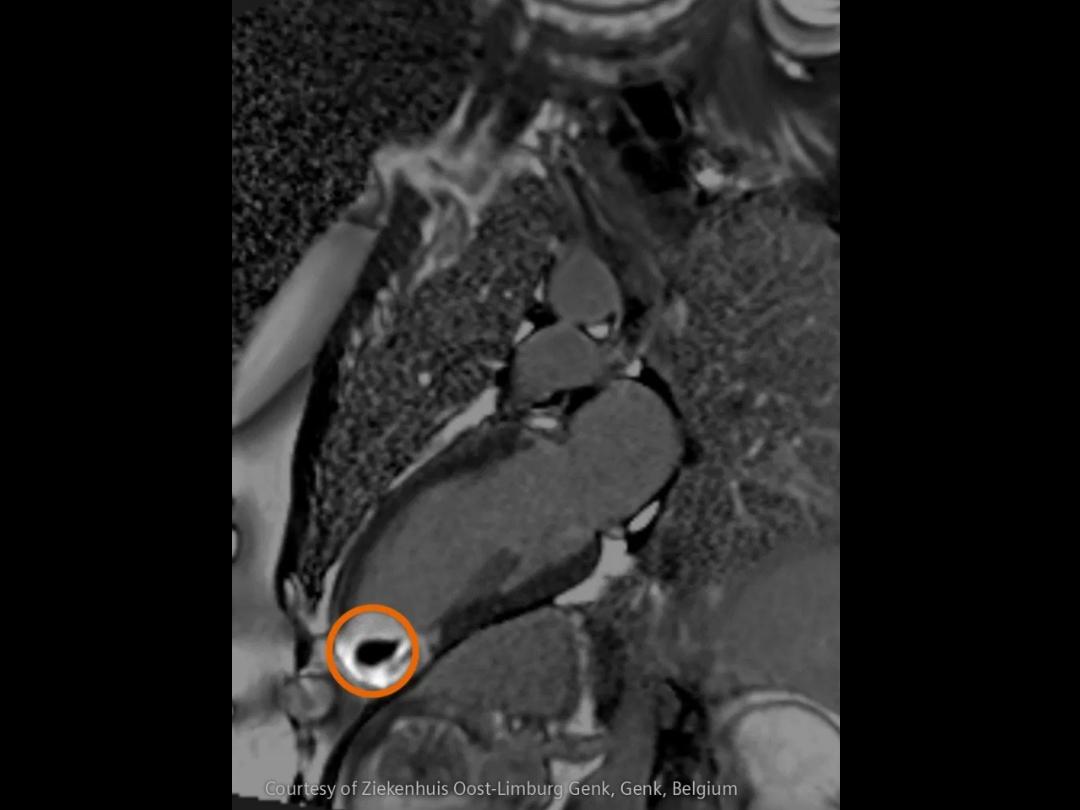

Im Bereich der Schlaganfallversorgung zählt jede Sekunde . Schnelle und präzise Bildgebung ist entscheidend, um das Ausmaß der Hirnschädigung zu beurteilen und die sofortige Behandlung einzusteuern. Angiographie, MRT, CT, Labordiagnostik und Ultraschall sind unverzichtbare Werkzeuge, um Schlaganfalltyp, -bereich und -schwere zu bestimmen. Durch technologische Fortschritte in der Bildgebung sind heute noch schnellere Aufnahmen, eine bessere Auflösung und eine optimierte Darstellung von Gehirnstrukturen und Blutgefäßen möglich. Innovationen wie Perfusionsbildgebung, Echtzeit-Gefäßkartierung und KI-gestützte Diagnostik revolutionieren die Abläufe bei Schlaganfällen und ermöglichen präzise zeitnahe Interventionen.